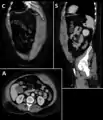

Rectus sheath hematoma seen on axial CT โ with active bleeding under Marcoumar- Rectus sheath hematoma as seen on ultrasound[2]